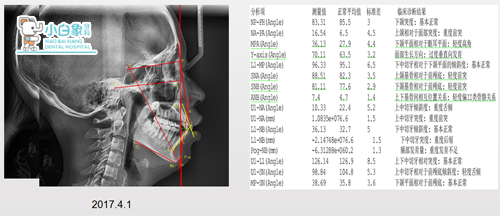

治疗前x线片

诊断

骨性二类

牙行一类

牙列拥挤

个别牙反合

牙龈炎